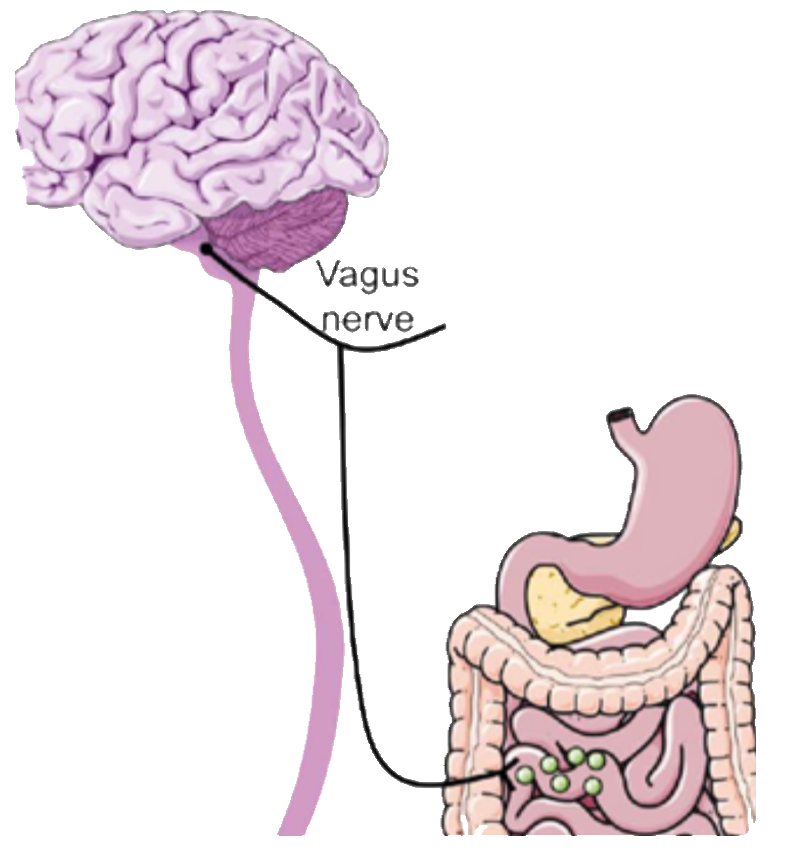

The main house cleaning mechanism of the small intestine is called MMC and is tightly regulated by the central nervous system itself, and mediated by the largest nerve of the human body, the vagus nerve. While describing this process here is of no use (it is fully detailed in MMC-SIBO chapter of the book), I need to pinpoint that there are several factors that may interfere with, delay or even inhibit completely MMC leading to bacterial overgrowth of the small intestine and as a result both upper and lower GI symptoms. Katherine fulfilled many prerequisites for MMC inhibition and thus the diagnostic panel was based on this hypothesis.

Migration motor complex

The cleaning machinery of the small intestine is regulated by the central nervous system itself. When in fasted state, muscular pulses directed by the brain forward all the debris produced by previous digestions from the small to the large intestine for elimination

- Hashimoto's thyroiditis may directly interfere with the Migrating Motor Complex which is crucial for small intestinal cleaning after meals

- All day eating is a common MMC inhibitor. MMC works better if the digestive tract is left to rest for at least 14 hours per day